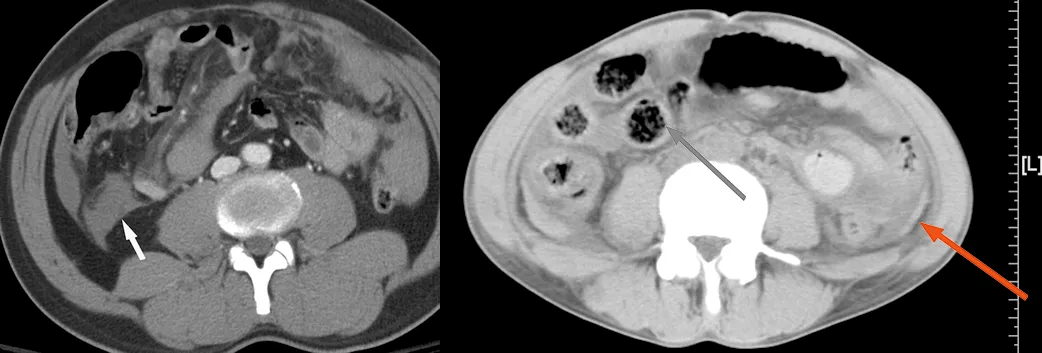

回盲部占位或炎症的影像鉴别诊断